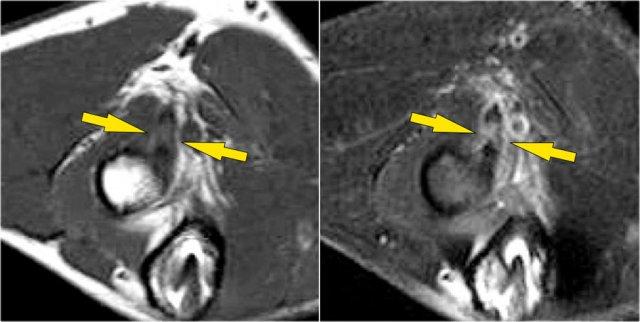

Đây là một ví dụ khác.

Trên hình ảnh T1W có một số dày lên và tín hiệu trung gian.

Đây có thể là thoái hóa gân, nhưng hãy luôn xem xét hình ảnh T2W để tìm kiếm vết rách.

Trong trường hợp này có một vết rách một phần.

Đây là một trường hợp khác.

Trên các hình ảnh mặt phẳng đứng dọc, chúng tôi không chắc chắn về một vết rách có thể xảy ra.

Có thể chỉ có một số thoái hóa gân hoặc viêm gân.

Các hình ảnh trục cho thấy rách một phần độ cao (mũi tên đỏ).

Luôn đảm bảo rằng mặt cắt ngang của bạn đi hết đến phần lồi củ xương, bởi vì nếu bạn dừng lại quá sớm, như trong trường hợp này, thì bạn sẽ chỉ thấy gân dày lên và một ít dịch, nhưng bạn không thể xác định được liệu có rách gân hay không.